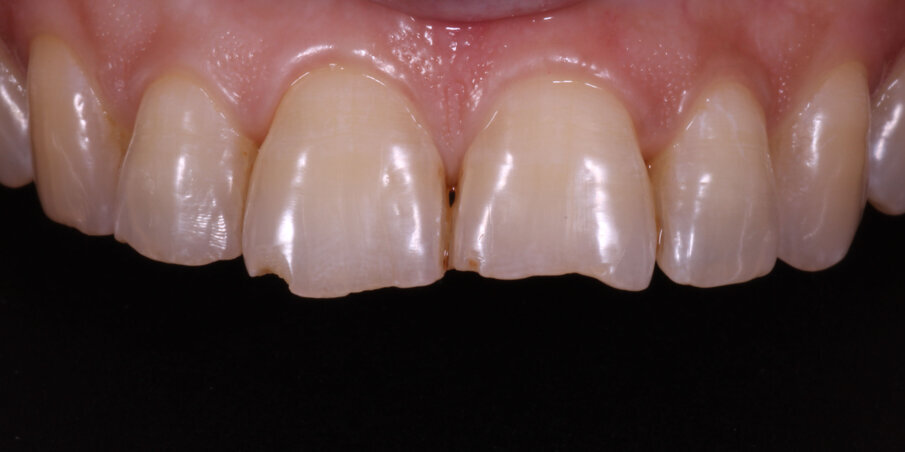

Finishing was carried out with finishing discs (Shofu Snap-on Discs) and Soflex Spirals (3M ESPE). Polishing was done with Prisma Gloss polishing paste (Dentsply) and a rubber cup (Fig 15). Thus the reverse smile was corrected by a simple restoration of fractured incisal edges. The patient reported back to us with a renewed sense of confidence after her smile-rejuvenation (Fig 16-17).

Fig 15. Post op image

Fig 16. Two-week post op

Fig 17. Final smile